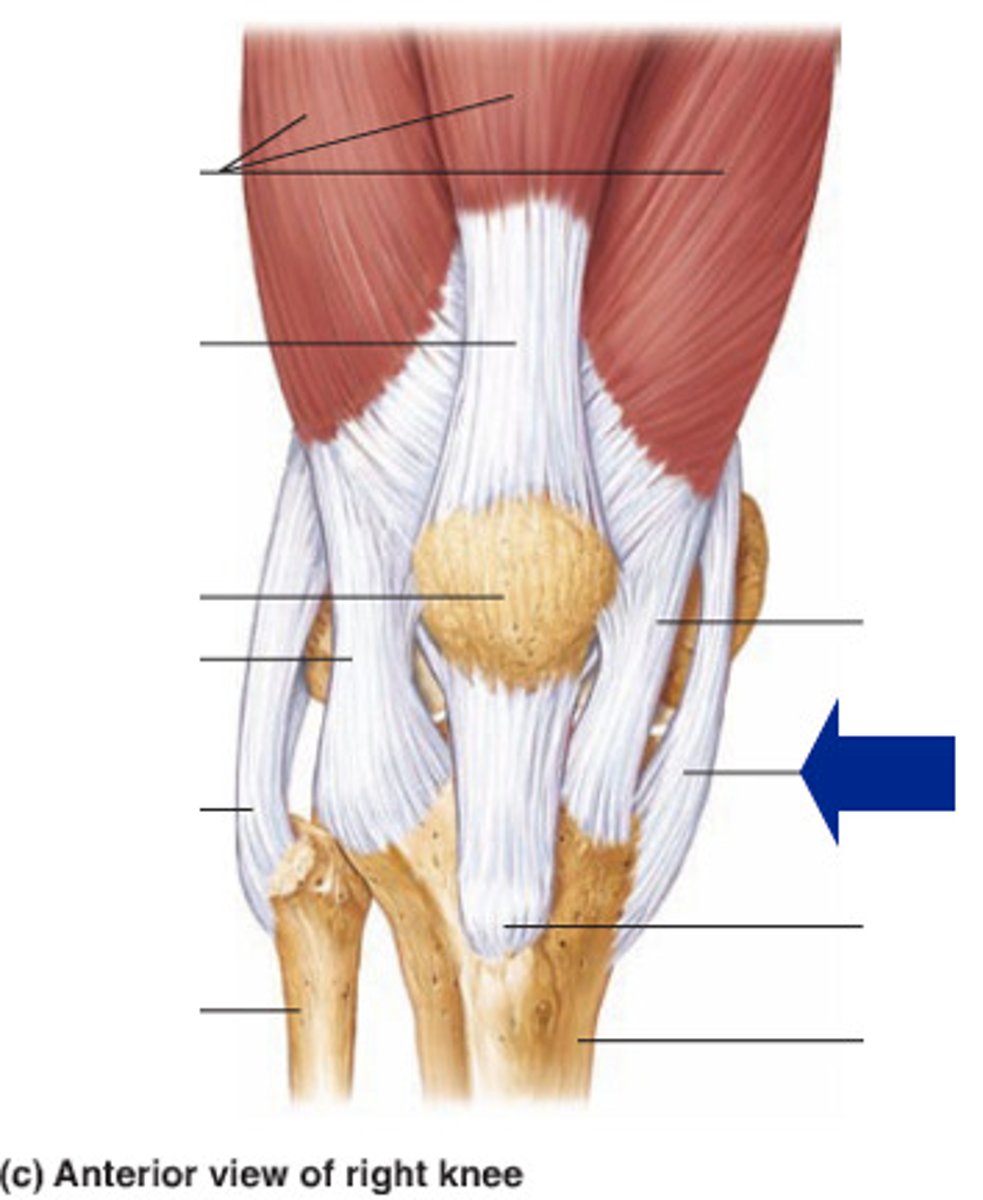

Quadriceps tendon

Patellar ligament

Medial meniscus

Lateral meniscus

Anterior cruciate ligament

Posterior cruciate ligament

Medial (tibial) collateral ligament

Lateral (fibular) collateral ligament